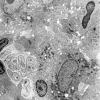

4 Leprosy – Tuberculoid (4)